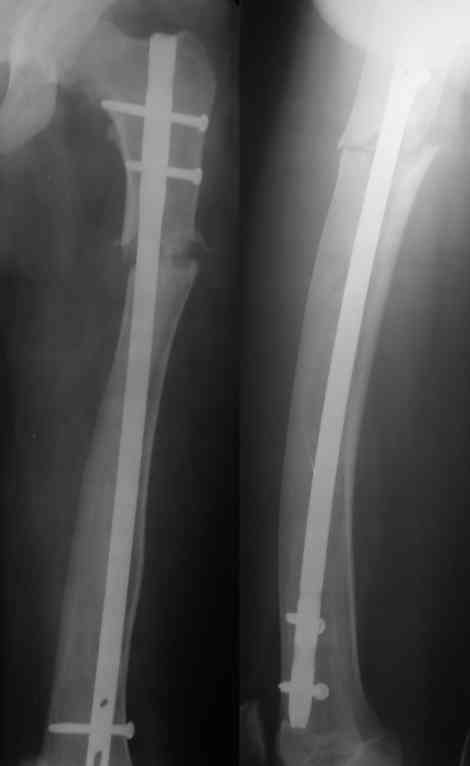

Закрыто заштифтовать не так просто - нужен серьезный опыт: помимо искривления оси бедра у таких больных обычно сужен косттномозговой канал, а сама кость в сечении саблевидная. Хотя механически это оптимально, но провести гвоздь достаточного диаметра для блокирования непросто. У нас была похожая пациентка весной - закончили пластиной. Снимки сейчас продемонстрировать не могу, но интересная фотография участка резецированной кости осталась - в приложении.

У нас был "похожий случай" патологический перелом деформированного бедра у подростка на фоне нейрофиброматоза, заштифтовали с небольшими трудностями.